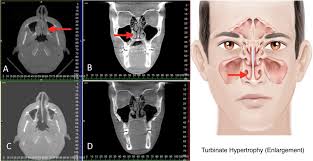

Normally these spaces are fairly open, but nasal polyps can grow large enough to block them. Urethral secretions are normal physiological like saliva in mouth whose role is to keep urethra moist when they are secreted excess they peep out as sticky fluid this excessive secretions most common. Epidemiology it is most commonly encountered in adults and rare in children. Nasal polyps are abnormal growths inside the nasal cavity or paranasal sinuses. Learn about causes, risks, home remedies, and.

Nasal polyps usually grow in the shape of a teardrop. They often occur in the area where the upper sinuses drain into your nose (where your eyes, nose, and cheekbones meet). The most common symptoms they cause are a stuffy, runny nose. I have nasal polyps may any one who can help me please. Small nasal polyps may not cause symptoms. They're not usually serious, but they can keep growing and block your nose if not treated. When too much mucus builds up in the sinuses, they can become. The nasal passage is important for filtering the air that we breathe in and it also stops tiny foreign particles or microorganisms from entering the body. Epidemiology it is most commonly encountered in adults and rare in children. Book a clinic visit today with solv. A polyp is an abnormal growth that arises from tissues in the mucous membrane. Nasal polyp is a prolapsed pedunculated part of the inflamed nasal mucosa and is completely inflammatory in origin. With nasal polyps, specifically, it's possible the cause is an increase in inflammation and swelling of the nasal passage.

They can make your nose feel stuffy, and can decrease your sense of smell. These have been subdivided into 4 stages. They're not usually serious, but they can keep growing and block your nose if not treated. Nasal polyps are polypoidal masses arising mainly from the mucous membranes of the nose and paranasal sinuses. Nasal polyps can grow anywhere on the lining of the nose or the sinuses.

Sinonasal polyposis refers to the presence of multiple benign polyps in the nasal cavity and paranasal sinuses. Read about the symptoms, causes, treatments and when to see a gp. Nasal polyps are polypoidal masses arising mainly from the mucous membranes of the nose and paranasal sinuses. They often grow where the sinuses open into the nasal cavity. Nasal polyps usually grow in the shape of a teardrop. Nasal polyps are soft, painless growths inside the nasal passages. Large polyps may cause difficulty breathing, infections, and an altered sense of smell. It is not a neoplasm.

I have tryed so many things please 0763543975. A polyp is an abnormal growth that arises from tissues in the mucous membrane. Larger ones can block normal drainage from the sinuses. In advanced cases, polyp may be seen hanging. A nasal polyp is a benign (noncancerous) tumor that grows from the lining of the nose or sinuses. Symptoms include trouble breathing through the nose, loss of smell, decreased taste, post nasal drip, and a runny nose. Read about the symptoms, causes, treatments and when to see a gp. A modification of this system includes one more stage i.e. I have nasal polyps may any one who can help me please. Small nasal polyps may not cause symptoms. Polyps are the most common expansile lesions of the nas. Nasal polyps usually grow in the shape of a teardrop. The majority of people with nasal polyps will experience nasal congestion, which may be severe and unable to be helped by typical allergy medications.